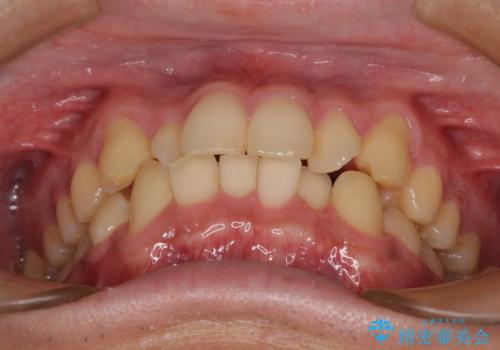

- 上下前歯の捻れやデコボコを気にして来院された患者様です。

マウスピース矯正でもワイヤー矯正でも対応可能でしたが、極力楽をして治したいとのことでワイヤー装置にて治療をおこなうこととしました。

口元はそれほど突出しておらず、患者様自身も気にしていらっしゃいませんでしたが、前歯の捻れやデコボコを解消すると、前方に拡大され、治療後に出っ歯仕上がりとなるリスクがあったため、補助装置により上顎臼歯を後方移動していくこととしました。